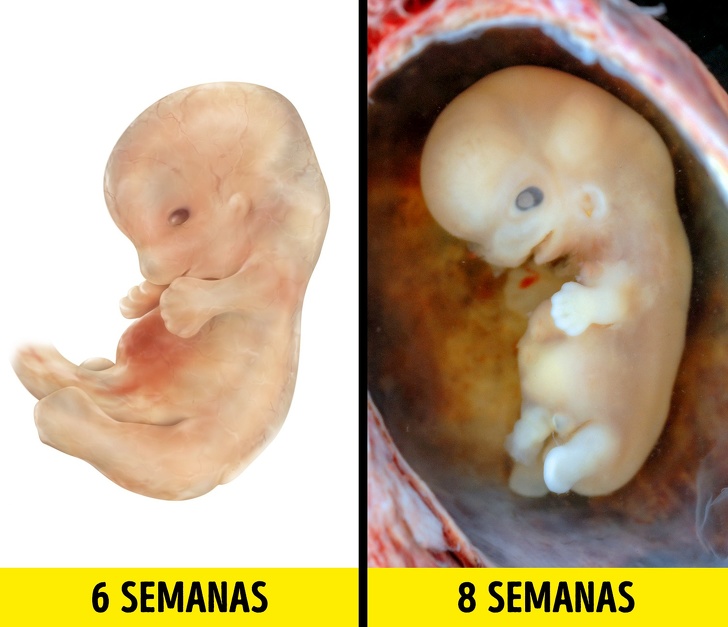

5-6 semanas

Ya para la quinta semana empiezan a aparecer las manos pero no se alcanzan a distinguir los dedos. Sin embargo, puede flexionar los brazos y piernas. Se forman los genitales externos aunque todavía no es posible ver el sexo en una ecografía. Ya ha crecido hasta 10 mil veces. Comienza a formarse la cara con los ojos, que permanecerán cerrados por más tiempo, y se oscurecen y a tomar más forma humana.

7-8 semanas

En la séptima semana de embarazo, el feto se mueve más pero es casi imperceptible para la madre. Las manos y pies con sus dedos se vuelven muy parecido a los de los adultos. Empieza a formar los rudimentos de los dientes leche y el sistema reproductivo. Además, los riñones comienzan a producir orina. Su tamaño es de 2,5 cm, tiene expresiones faciales, párpados y está más definida la punta de la nariz.